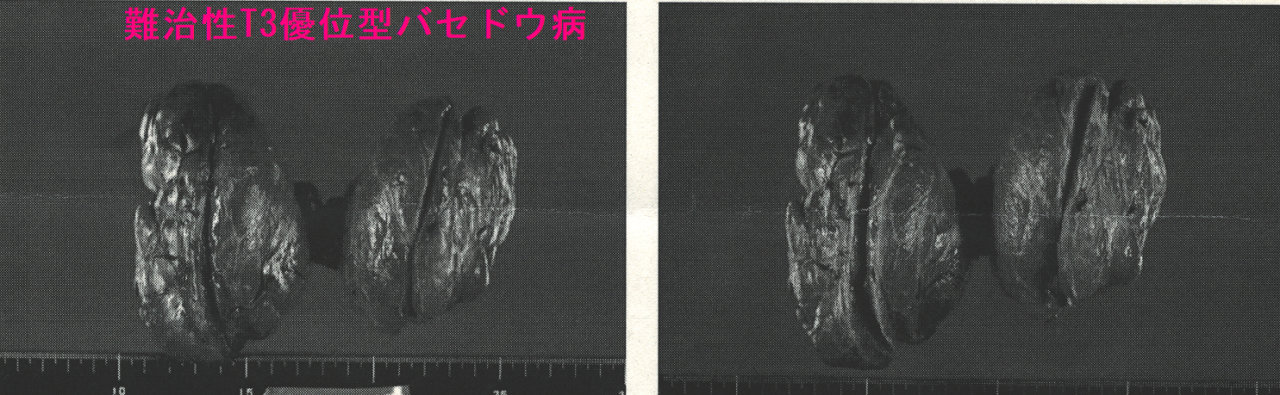

ケース④ 一度も甲状腺機能正常化したことが無く、甲状腺全摘手術に

難治性T3優位型バセドウ病 下甲状腺動脈血流速度(ITA-PSV)も高値で85.3cm/sでした。

下は、手術標本。一部、エコーでも写らなかった乳頭状増殖(□)を認めたが、悪性所見なし。